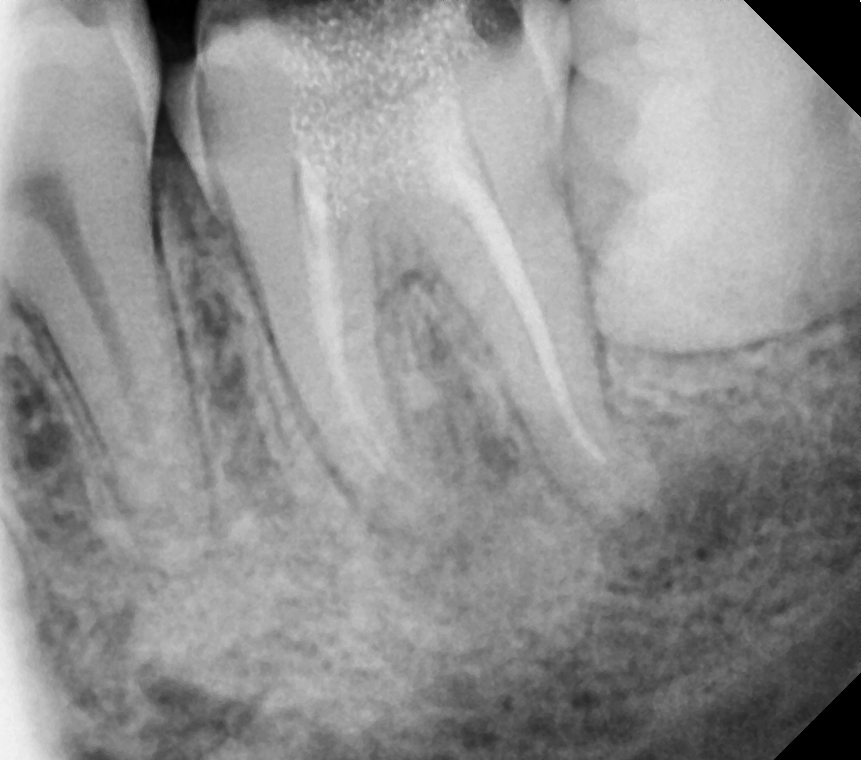

• A diagnosis is made for the tooth with percussion, palpation and cold tests and an x-ray.

• Once it is confirmed that the tooth requires root canal treatment.

• After anesthesia given, a small opening on the top of the tooth to clean the root canal with small files

• We rinse the tooth with antibacterial solutions to eliminate the bacteria

• We leave medicine inside the tooth and place a temporary filling on top